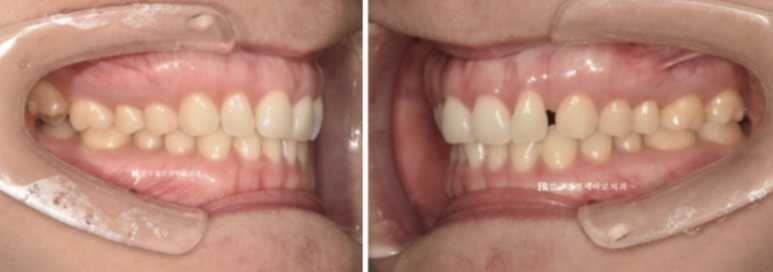

23년 7월부터 23년 12월까지 약 5개월에 걸쳐서 1차세트 장치 14개를 다 착용한 후 모습입니다

23.12

가위교합과 벌어졌던 공간은 이미 해결이 되엇습니다.

중심선도 잘 맞습니다.

블랙 트라이앵글과 치아 사이 미세공간 마무리를 위해 추가적인 제작에 들어갑니다.

가위교합은 1차 세트에서 완전히 개선이 되었기에 미니스크류는 추가장치 제작을 하기로 한 날 제거했습니다.